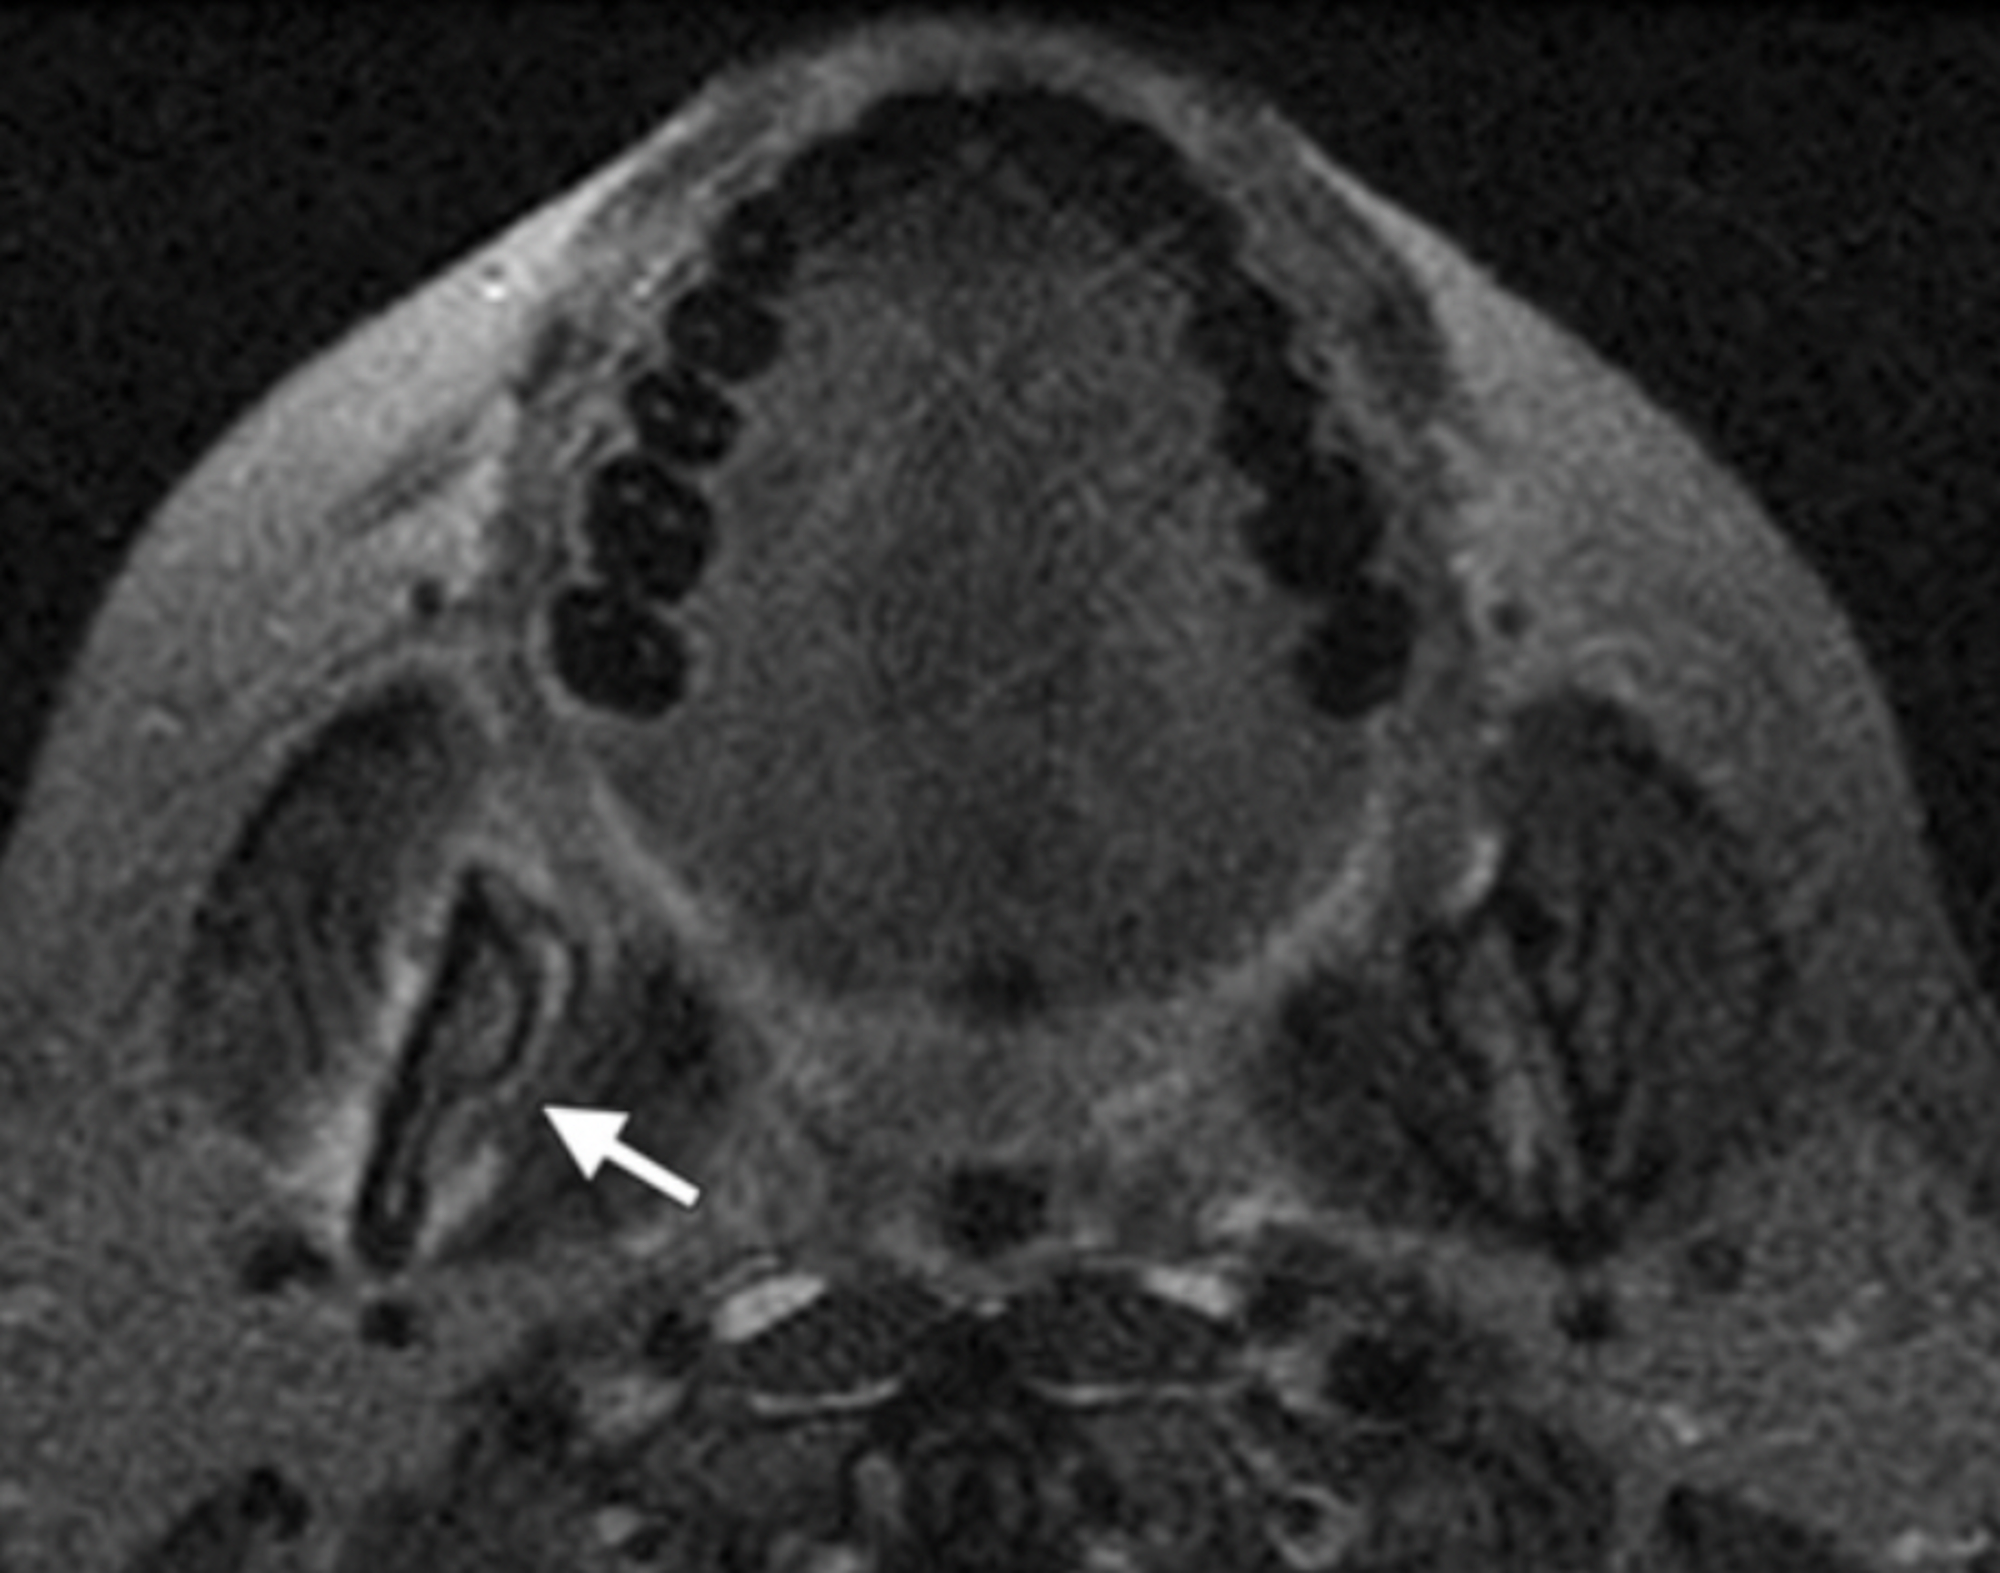

Imaging Findings of BisphosphonateAssociated Osteonecrosis of the Jaws Jaw Osteonecrosis Imaging Advances in imaging include the use of cone beam computerized tomography assessing cortical and cancellous architecture. Osteonecrosis of the jaw has been reported to manifest six to 60 months after the initiation of bisphosphonate treatment. Osteonecrosis of the jaws can result either from radiation, used in radiotherapy for treatment of malignant tumors, or. This work provides a systematic review of. Jaw Osteonecrosis Imaging.

Figure 2 from Imaging Findings of BisphosphonateRelated Osteonecrosis Jaw Osteonecrosis Imaging Osteonecrosis of the jaws can result either from radiation, used in radiotherapy for treatment of malignant tumors, or. Osteonecrosis of the jaw has been reported to manifest six to 60 months after the initiation of bisphosphonate treatment. Advances in imaging include the use of cone beam computerized tomography assessing cortical and cancellous architecture. This paper is an adaptation of the. Jaw Osteonecrosis Imaging.

Medicationrelated osteonecrosis of the jaw Image Jaw Osteonecrosis Imaging Osteonecrosis of the jaw has been reported to manifest six to 60 months after the initiation of bisphosphonate treatment. Osteonecrosis of the jaws can result either from radiation, used in radiotherapy for treatment of malignant tumors, or. This work provides a systematic review of the literature from january 2003 to april 2014 pertaining to the incidence, pathophysiology,. Advances in imaging. Jaw Osteonecrosis Imaging.